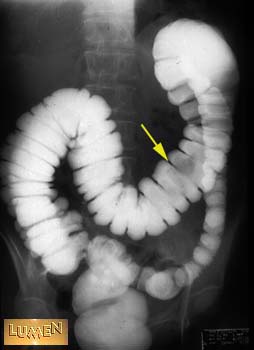

Question: What is the name of the sacs that produce the folds?

Haustra.